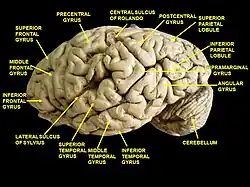

Drawing of a cast to illustrate the relations of the brain to the skull. (Inferior temporal gyrus labeled at center, in green section.) | |

Lateral view of a human brain, main gyri labeled. Cerebrum. Lateral view. Deep dissection. Inferior temporal gyrus labeled at bottom center.

Cerebrum. Lateral view. Deep dissection. Inferior temporal gyrus labeled at bottom center. Inferior temporal gyrus, right hemisphere.